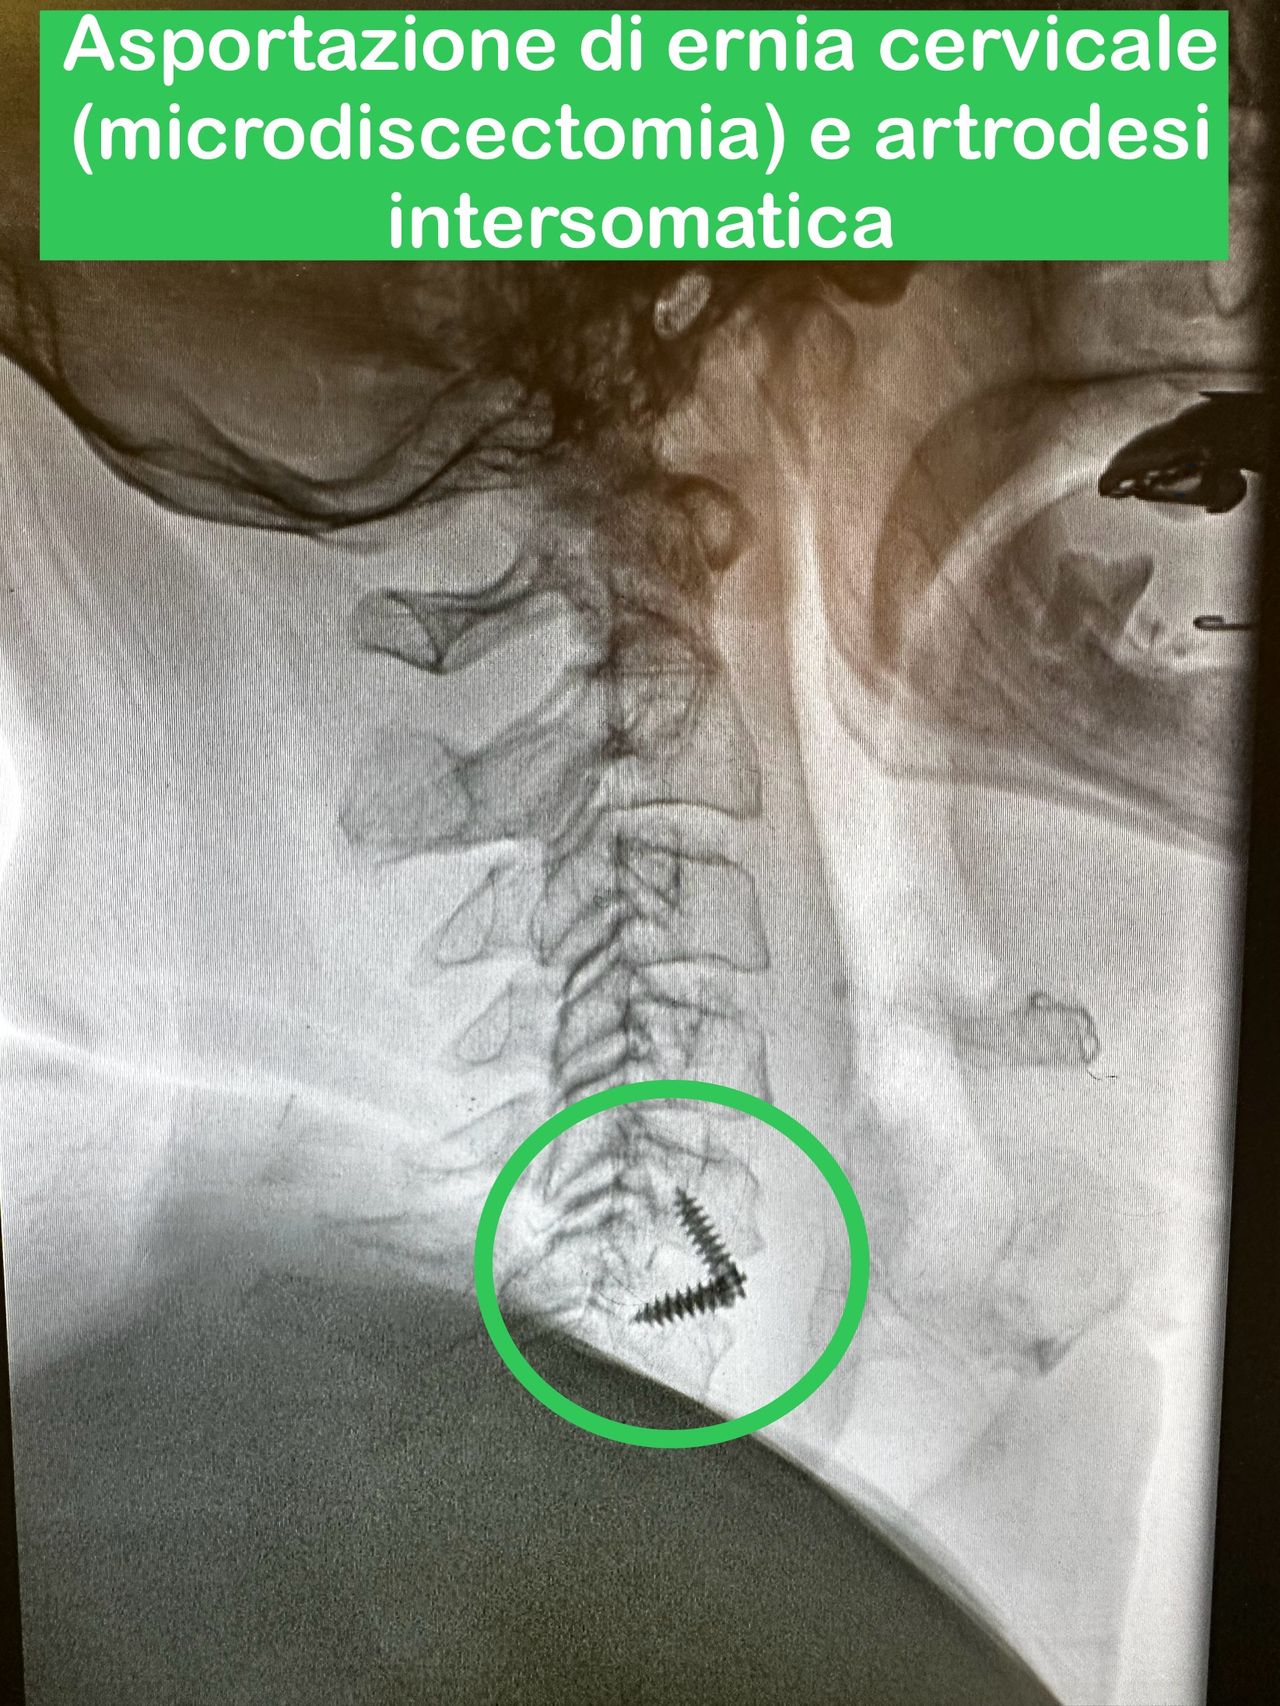

- Microchirurgia vertebrale

Microchirurgia dell’ernia cervicale e lombosacrale con con dimissione entro 24-48 ore

- Chirurgia Mininvasiva percutanea vertebrale - stabilizzazioni e artrodesi intersomatiche (per fratture vertebrali, spondilolistesi, instabilità vertebrali, discopatie)